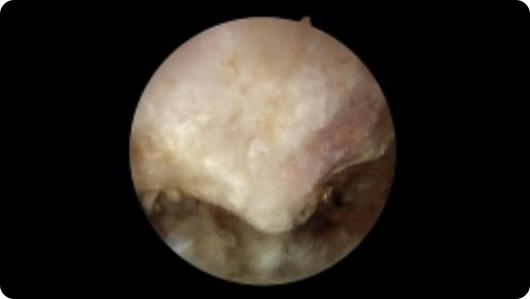

This page contains arthroscopic and radiography images of joint injuries and conditions, and the surgical repairs performed by Dr. Joshua Landau.

Arthroscopic image of a miniscus tear Arthroscopic image of a miniscus tear after knee arthroscopy Arthroscopic image of a bone spur Arthroscopic image of a removed bone spur Arthroscopic image of a shoulder dislocation Arthroscopic image of a repaired shoulder dislocation Arthroscopic image of a rotator cuff tear Arthroscopic image of a repaired rotator cuff

Miniscus Tear

After Knee Arthroscopy

Bone Spur

Bone Spur Removed